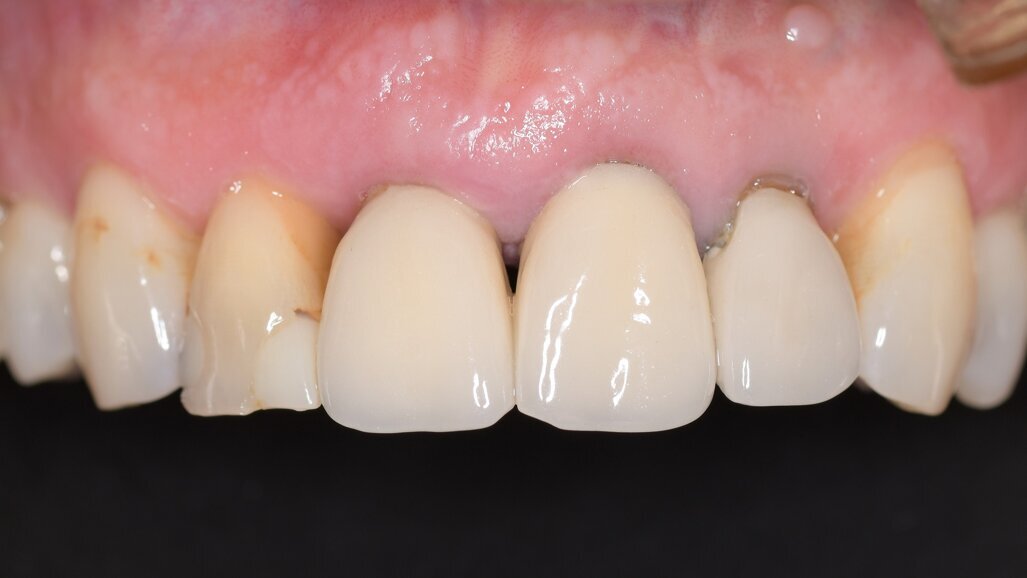

A 62-year-old male patient was referred to my practice for implant planning and treatment in the maxillary anterior region. The teeth in the maxillary anterior region had all undergone endodontic therapy, and teeth #11-22 had received crowns owing to an accident that had occurred 30 years before. The patient reported pain and was conscious that tooth #21 was mobile (Figs. 1a & b).

Fig. 1b: Initial situation.